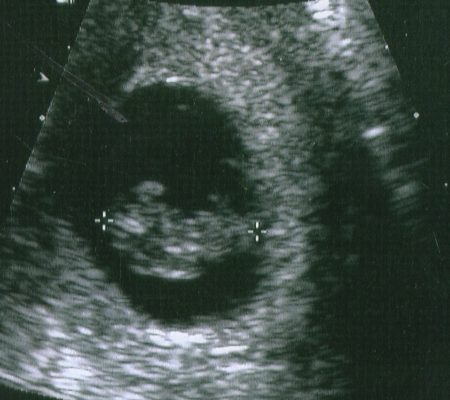

The initial ultrasound was also abnormal. The lady performing the test kept making perplexed faces and that was very frustrating to endure when they aren’t allowed to answer questions or tell you that something is wrong. After she finished she led me to a private room and said that a doctor would call on the telephone shortly. That is how I found out my baby would die. Alone in a strange room, talking on the phone with a doctor that I had never met nor never would, as he’s recommending an abortion.

I chose to continue the pregnancy. They did not know specifically what would be wrong and I was okay with that. They did, however, tell me that I would likely miscarry within the first 16 weeks, but they were wrong.

Each ultrasound there was another thing wrong. He’s too small. The amniotic fluid is low. He’s missing part of his brain……and so on. I stopped making those visits for a little while because it just became too much. And then when I did go back he had grown the part of his brain that was previously missing. I declined an amniocentesis because it didn’t matter to me what he had and I didn’t want to increase my risk of having a miscarriage.